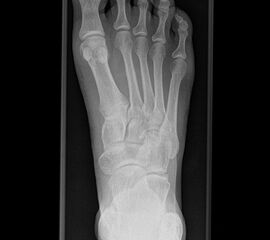

Besondere Bemerkungen zum Beispielbild:

• Schwere Hallux valgus Deformität.

• Die Sesambeine sind luxiert, ebenso das Großzehengrundgelenk. Luxation des Metatarsophalangealgelenks II.

• Degenerative Veränderungen der tarsometatarsalen (TMT) Gelenkreihe, betont TMT II und III.